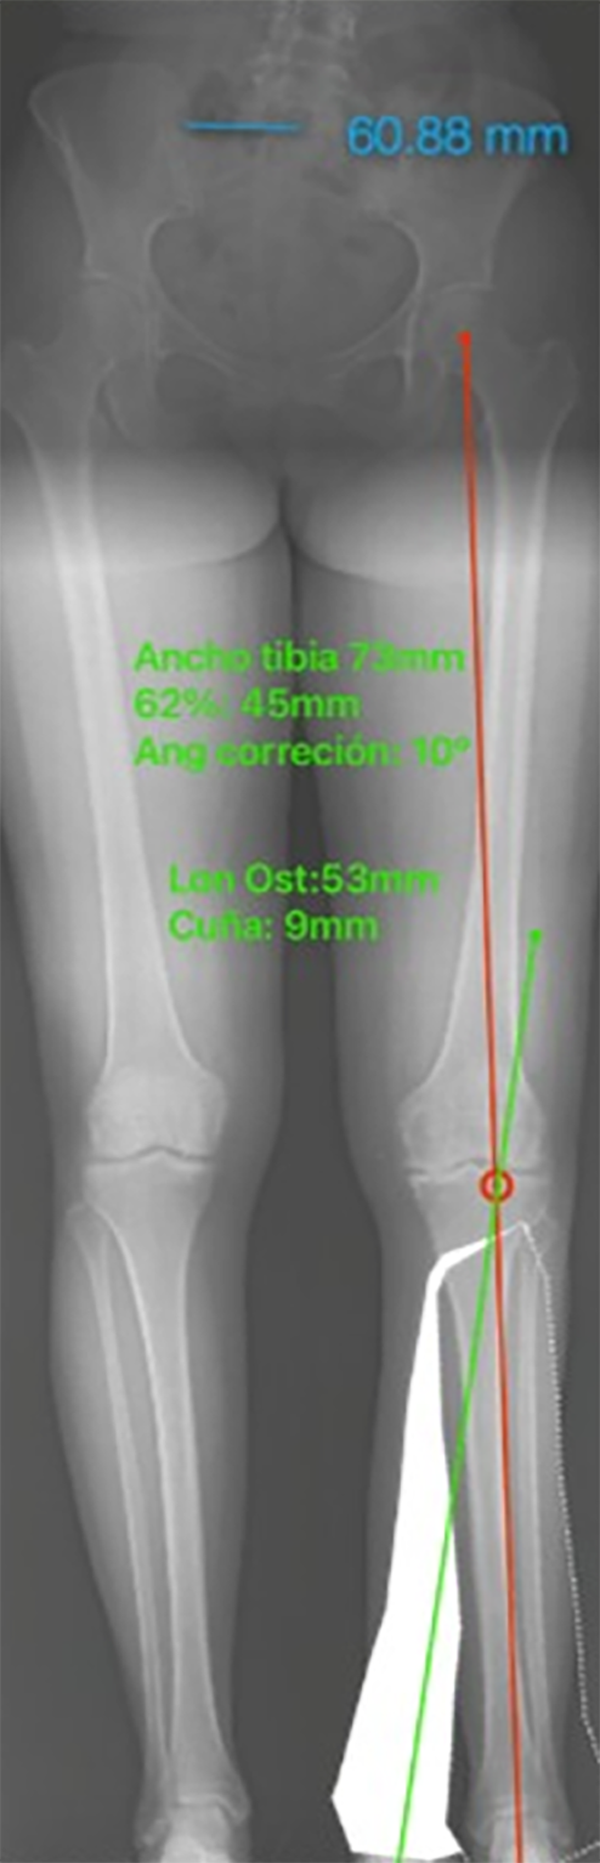

Determinar el punto de corrección. Trazar una línea desde el centro de la cadera y el centro del tobillo dirigidos a este punto, la intersección de estas líneas son el grado de corrección. Punto de corrección: ancho de tibia 73 mm (62%: 45 mm), 10° de corrección.

Figura 26: Imagen correspondiente al Paso 3.

La radiografía panorámica postoperatoria se observa en la línea de carga del miembro inferior izquierdo, que pasa por el 62% del ancho de los platillos tibiales, ubicada a 45 mm, desde el platillo medial.

Con el software se corrobora esta medida, comprobando la exactitud del método de planeamiento y su resultado, también el MPTA resultante de 93°, que es exactamente el mismo calculado en el planeamiento (fig. 30).

Figura 30: Resultados postoperatorios.